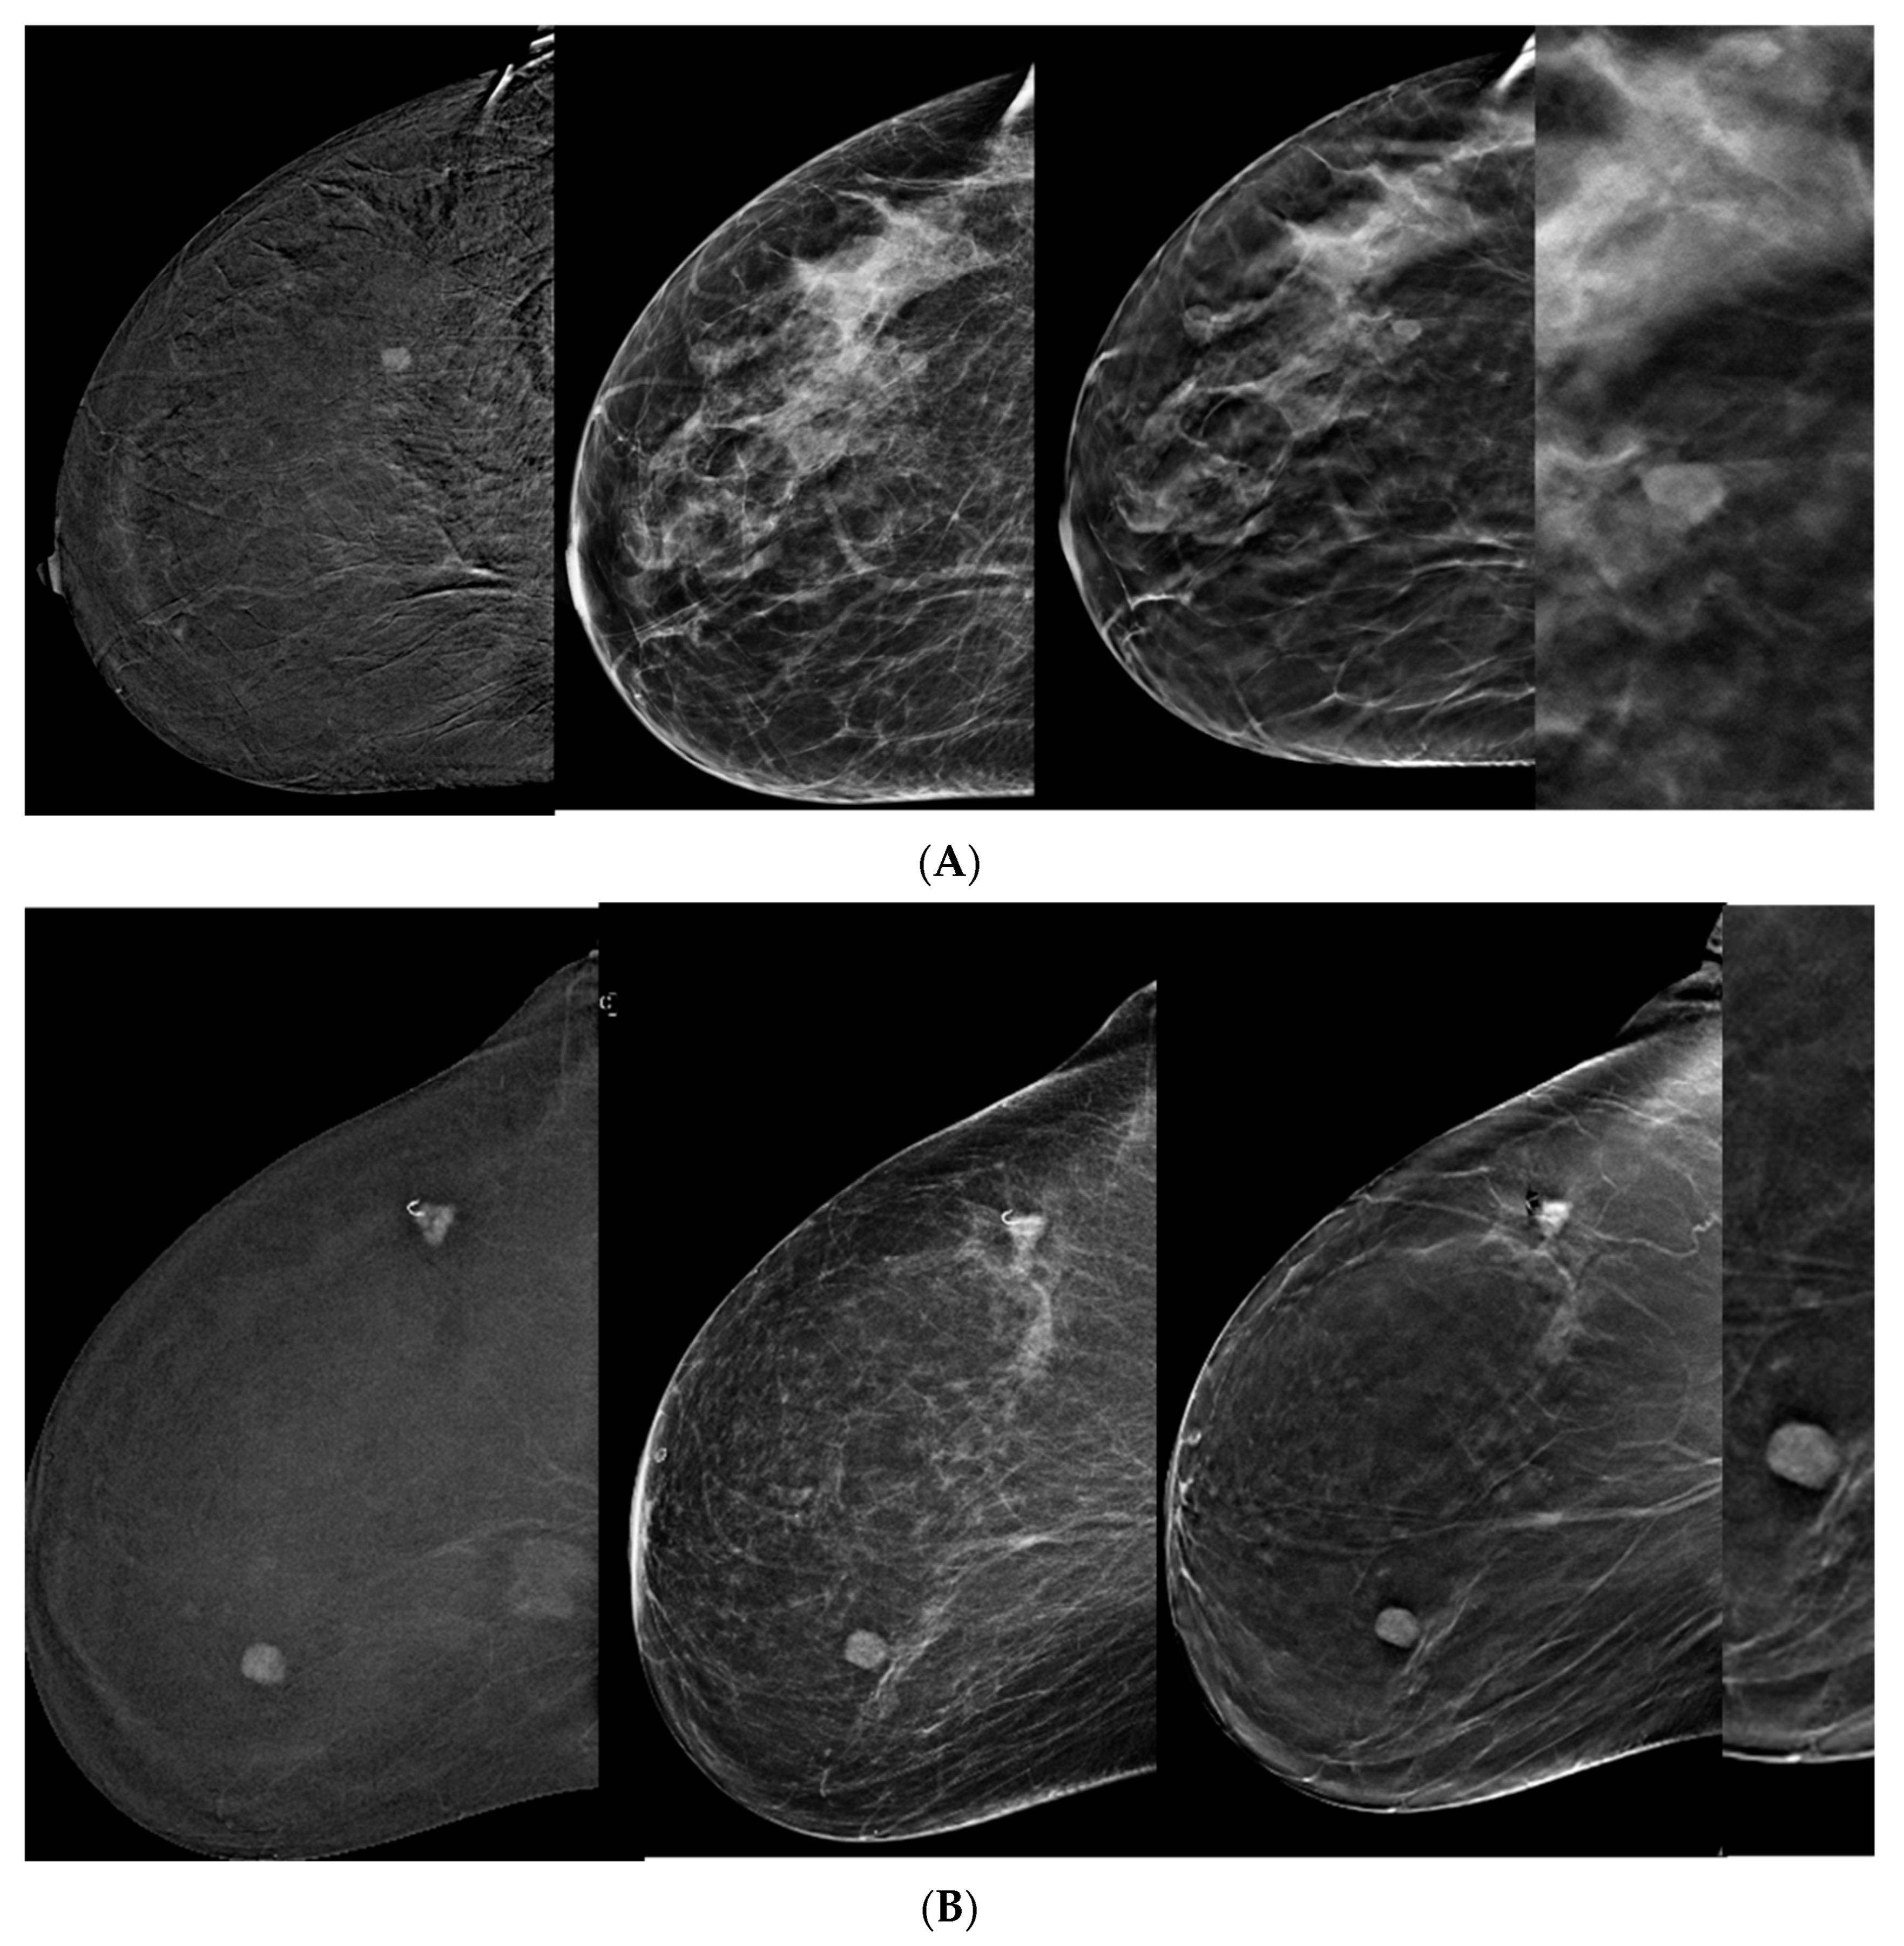

- Incorporating DBT into CEM-detected lesions leads to a significant upgrade in BIRADS scores toward the lesion’s true pathology (p > 0.0001).

- This was consistent across all readers, with particularly notable differences observed among less experienced readers.

- The primary driver for the score upgrade was attributed to improved margin visibility facilitated by DBT.